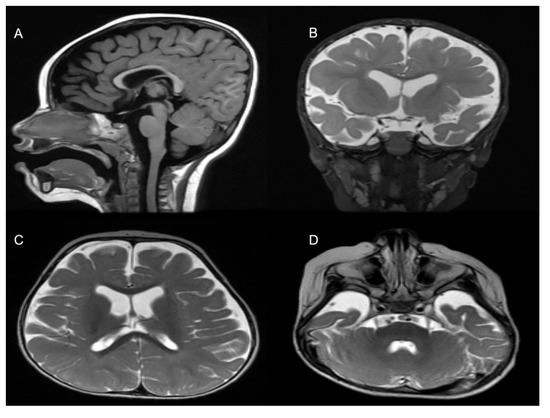

Figure 3.

MRI Findings. (A) Mild thinning of the corpus callosum. Selected coronal T2 (B) and axial T2-weighted images (C,D) show volume loss of the cerebral hemispheres with resultant mild expansion of the lateral ventricles and CSF spaces.

The patient was generated by in vitro fertilization from healthy consanguineous parents with a history of infertility. She was born at term after an uneventful pregnancy, with a normal birth weight. The patient started showing symptoms at 4 months of age, when she was not able to support her head, roll over, make sounds, or follow subjects. She failed to gain any of her developmental milestones including gross and fine motor function, cognition, and speech. She had multiple choking episodes, mainly with liquids and only tolerated a pure diet. She had constipation. Her first attack of seizure was at the age of 16 months, after a febrile illness, and she continued to suffer multiple brief myoclonic seizures, which were partially controlled with levetiracetam. Assessment at the age of 18 months was remarkable for facial dysmorphism in the form of bifrontal narrowing, epicanthal fold, almond-shaped eyes, long palpebral fissures, low-set ears, protruded tongue, and nystagmus. The growth parameters were within the percentiles for age and gender (head circumference 46 cm (25th percentile), weight 9 kg (10th percentile), and length 90 cm (>90th percentile). Neurological deficit was evident, with central hypotonia, peripheral limbs spasticity, hyperreflexia, and positive clonus. An ophthalmological exam was positive for moderate rod–cone dystrophy. Brain magnetic resonance imaging (MRI) at the age of 12 months showed a global mild volume loss of the cerebral hemispheres with a resultant mild expansion of the lateral ventricles and CSF spaces, a mildly thin but well-formed corpus callosum, a normal volume and appearance of the brainstem and cerebellum, and appropriate myelination (based on the patient’s age). Moreover, the brain showed normal signal characteristics without cortical, structural, or migration abnormalities (Figure 3). Hearing assessment was normal.

Since the first case of a pathogenic DNM1 variant was discovered nearly a decade ago, most of the cases were reported to be in autosomal dominant mode, caused by heterozygous deleterious variants. The only exception to this was the study describing two unrelated DEE cases harboring loss-of-function nonsense variants in a homozygous state [12]. Interestingly, both nonsense variants in Yigit et al. (2022) study caused an immediate stop codons (c.97C>T; p.Gln33* in family 1, and c.850C>T; p.Gln284* in family 2) in DNM1 which led to an early truncation of DNM1. Both patients presented with a severe neurodevelopmental phenotype in the form of hypotonia, visual impairment, uncontrolled seizure, and microcephaly, in addition to agenesis of the corpus callosum in one of them. Our patient presented with a global developmental delay, severe hypotonia, notable hyperreflexia, nystagmus, and facial dysmorphism. Moreover, the neuroimaging of our patient showed a global mild volume loss in the cerebral hemispheres with a resultant mild expansion of the lateral ventricles and CSF spaces, in addition to mild agenesis of the corpus callosum, but the rest of the brain was mostly unremarkable, in comparison to Yigit et al. (2022) cases [12]. Interestingly, the novel deletion also resides in the GTPase domain, similar to the other loss-of-function variants reported before [8].